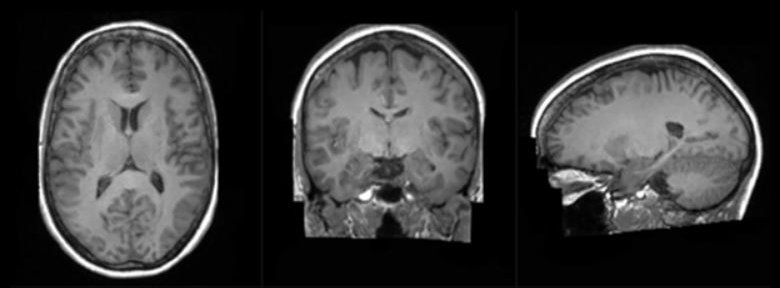

합성된 3D 뇌 이미지는 남성 또는 여성, 젊은이 또는 노인의 이미지일 수 있으며 연구 요구 사항에 따라 주문 제작할 수 있다. 이미지가 시뮬레이션되었지만 연구원들은 고도로 훈련된 알고리즘의 결과로 실제 뇌 스캔처럼 보이고 반응한다고 주장했다.

이 연구는 뇌 질환을 암시할 수 있는 뇌 이미지의 이상한 구조를 식별하기 위한 프로젝트로 시작됐다. 연구팀은 먼저 건강한 뇌의 실제 이미지를 보여주고 건강하지 않은 뇌의 이미지를 추적해 AI 모델을 훈련했다. 또한 합성 이미지를 생성하기 위해 나이든 두뇌와 젊은 두뇌의 차이점을 모델에 가르쳤다. 엔비디아에 따르면 아주 큰 데이터 세트를 사용해 이미지 정확도가 향상됐고 모델이 실제 이미지만큼 결과를 잘 예측할 수 있도록 최적화됐다.